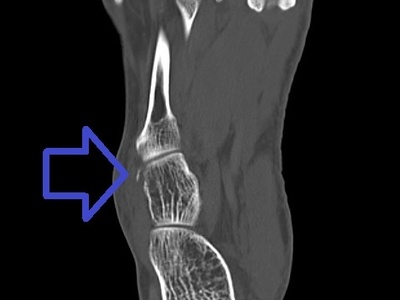

Calcaneus

Calcaneus is the heel bone that absorbs ground reaction forces and anchors the Achilles tendon. It develops from a primary ossification center; fractures are serious, often intra-articular, and can cause long-term foot disability.